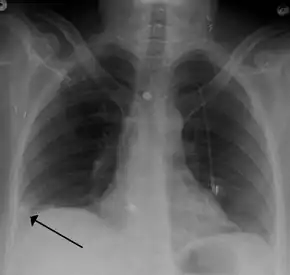

Pulmonary embolism (white arrow) that have been long-standing and has caused a lung infarction (black arrow) seen as a reverse halo sign.

- Chest X-rays are often done on people with shortness of breath to help rule-out other causes, such as congestive heart failure and rib fracture. Chest X-rays in PE are rarely normal,[60] but usually lack signs that suggest the diagnosis of PE (for example, Westermark sign, Hampton's hump).